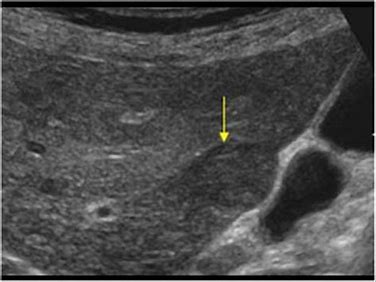

Ultrasound view...canine liver.

Dr. Brown performs an ultrasound as part of a diagnostic office visit to determine what internal problems may exist causing this cat to have urinary incontinence and difficulty.